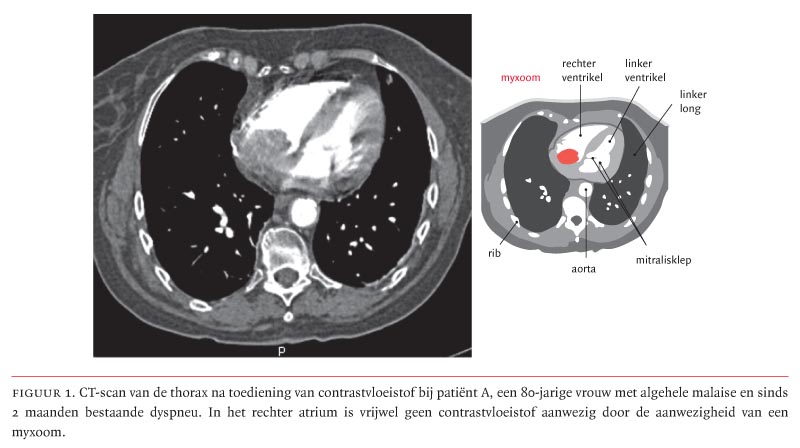

Een 80-jarige vrouw met kortademigheid door myxoma cordis ...

Een 80-jarige vrouw met kortademigheid door myxoma cordis ... from www.ntvg.nl